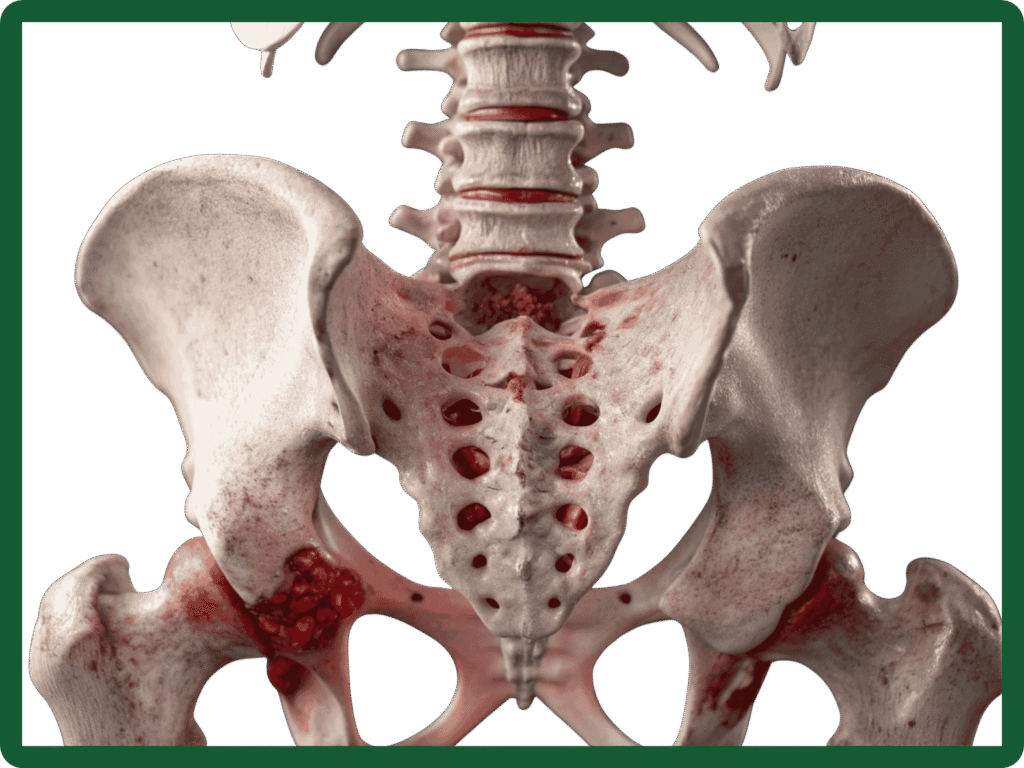

Hip arthritis is the wear-and-tear or inflammation of the hip joint that leads to pain, stiffness and reduced mobility. The hip is a ball-and-socket joint formed by the head of the femur (thigh bone) and the acetabulum (socket) of the pelvis. When the cartilage that cushions the joint wears away, bones rub together, causing pain and limiting everyday activities.

- Osteoarthritis (degenerative): The most common type where cartilage breaks down with age or overuse.

- Avascular necrosis (osteonecrosis): Loss of blood supply to the femoral head leading to collapse and secondary arthritis.